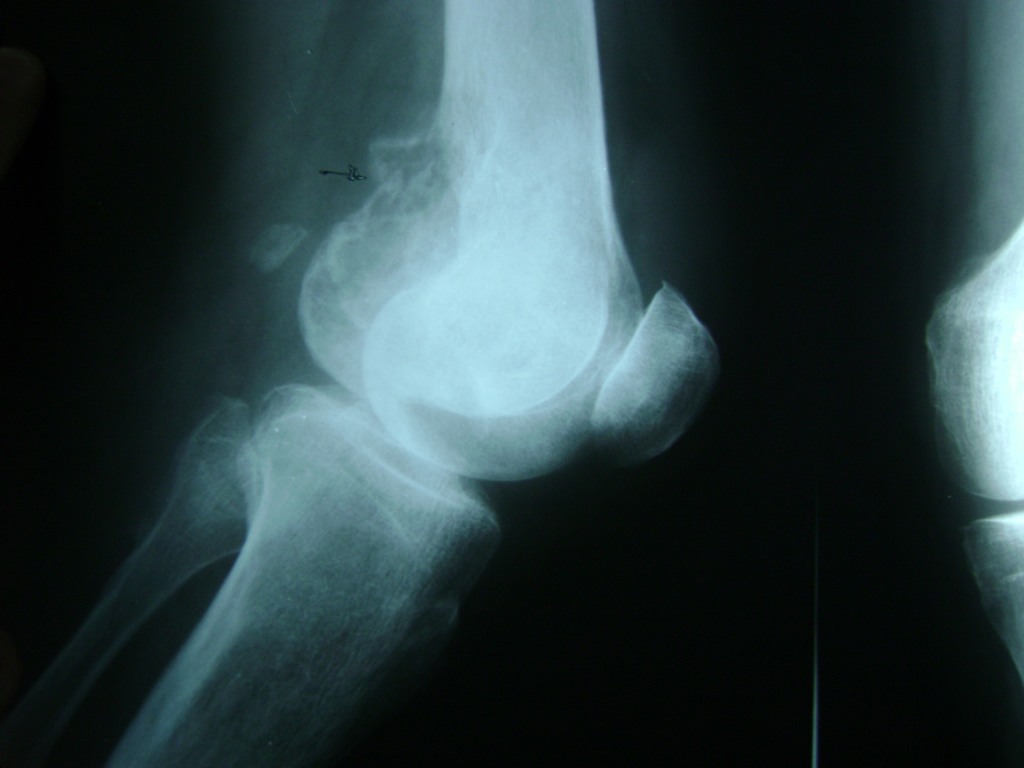

La artroscopia de rodilla es un cirugía en el cual la estructura interna de la articulación es examinada ya sea para realizar un diagnostico o para realizar un tratamiento, este procedimiento se realiza utilizando un instrumento parecido a un pequeño tubo llamado artroscopio.

La artroscopia se popularizo en 1960 y hoy en día es muy común en todo el mundo. Típicamente, es realizada por cirujanos ortopédicos de manera ambulatoria. Cuando se realiza de manera ambulatoria los pacientes pueden regresar a casa después de la operación, no se requiere quedarse en hospital.